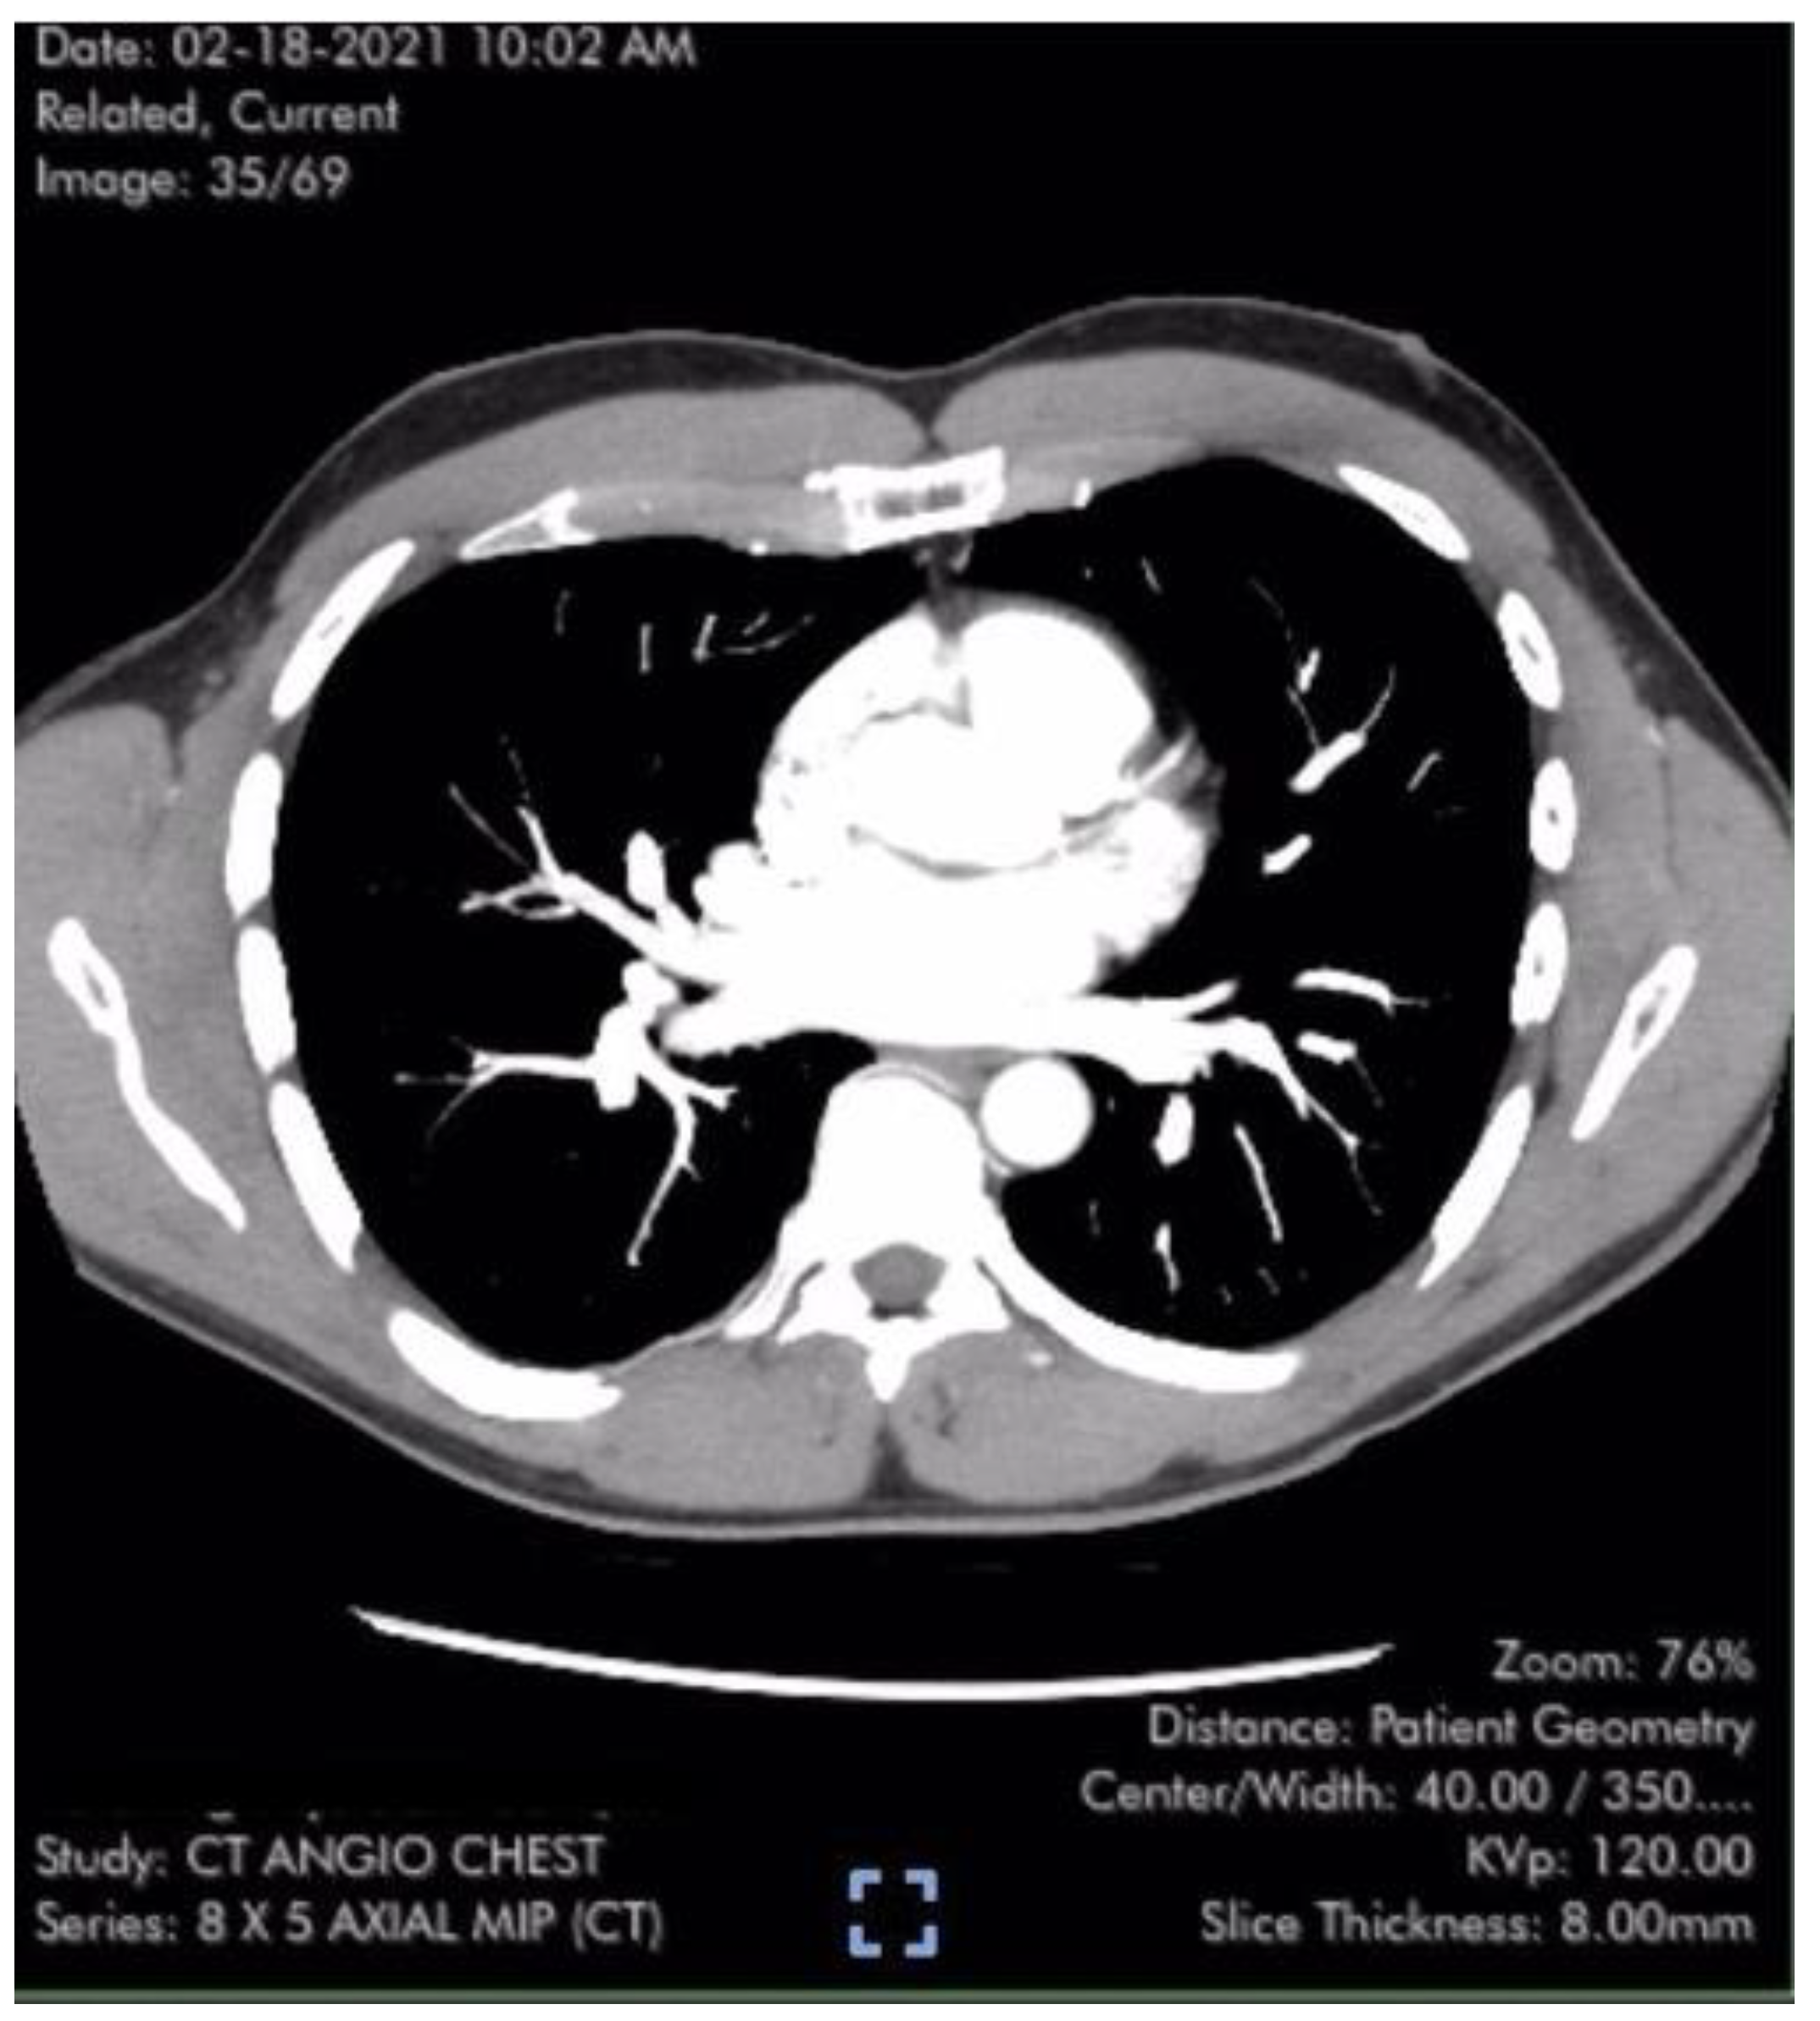

Figure 1.

Axial CT image of the Case #1 patient from normal 3-dimensional pulmonary artery reconstruction without evidence of arterial clots or pulmonary emboli [6,7].

Case #1 is a previously healthy 49-year-old male physician athlete, body mass index (BMI) 23, non-smoker with a history of mild exercise-induced asthma treated with albuterol. The patient completed the primary series of Pfizer mRNA COVID-19 vaccine (BNT162b2), Dose 1 in December 2020 and Dose 2 in January 2021. Approximately three weeks after the second dose, the patient suddenly developed severe fatigue, flu-like symptoms, tachycardia, palpitations, orthostasis, right-sided chest pressure and dyspnea on exertion. SARS-CoV-2 polymerase chain reaction (PCR) testing was negative at the time of the onset of these symptoms. Transthoracic echocardiogram revealed normal left ventricular function with an ejection fraction (EF) of 65%, normal right ventricular size and function and a maximal tricuspid regurgitation velocity (TRVmax) of 3.09 m/s. The estimated right ventricular systolic pressure (RVSP) of 42 mmHg was interpreted as mild/moderate pulmonary hypertension (Table 1). Laboratory studies including measurement of brain natriuretic peptide (BNP) (22 pg/mL; reference range < 900 pg/mL) were unremarkable except for elevated low-density lipoprotein (LDL) cholesterol and a hematocrit of 50%. Pulmonary computer tomography (CT) angiogram with 3D reconstruction of the PA tree was normal without evidence of pulmonary clots (Figure 1). The patient subsequently developed 15 lbs of fluid gain and generalized swelling, neck pressure, headaches and a feeling of “being hung upside down” consistent with jugular vein distention (JVD) and cerebral venous congestion. The resting oxygen saturation (SpO2) was 92% and there was new onset systolic and diastolic arterial hypertension. Symptoms and chest pressure occurred at rest and were exacerbated by exertion. Exercise and functional limitations were consistent with New York Heart Association (NYHA) Class 3–4. Serial echocardiograms showed no worsening of RVSP and continued normal RV function (Table 1). Symptoms and exercise tolerance improved to NYHA class 1–2 over one year. Fluid weight gain, swelling, tachycardia and arterial hypertension resolved and the resting SpO2 increased to 98–100%. Flu-like symptoms and fatigue diminished but did not disappear. RVSP remained elevated and essentially unchanged by follow up echocardiography (Table 1). This case was reported to the Vaccine Adverse Event Reporting System (VAERS ID 1039123).